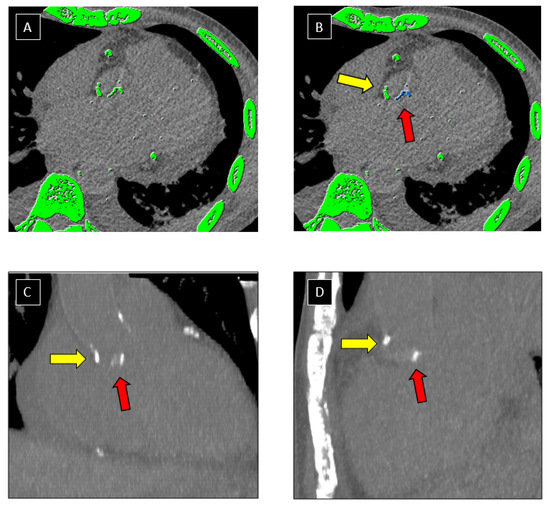

3.2.1. Patients with Native Mitral IE

3.2.2. Patients with Native Aortic IE